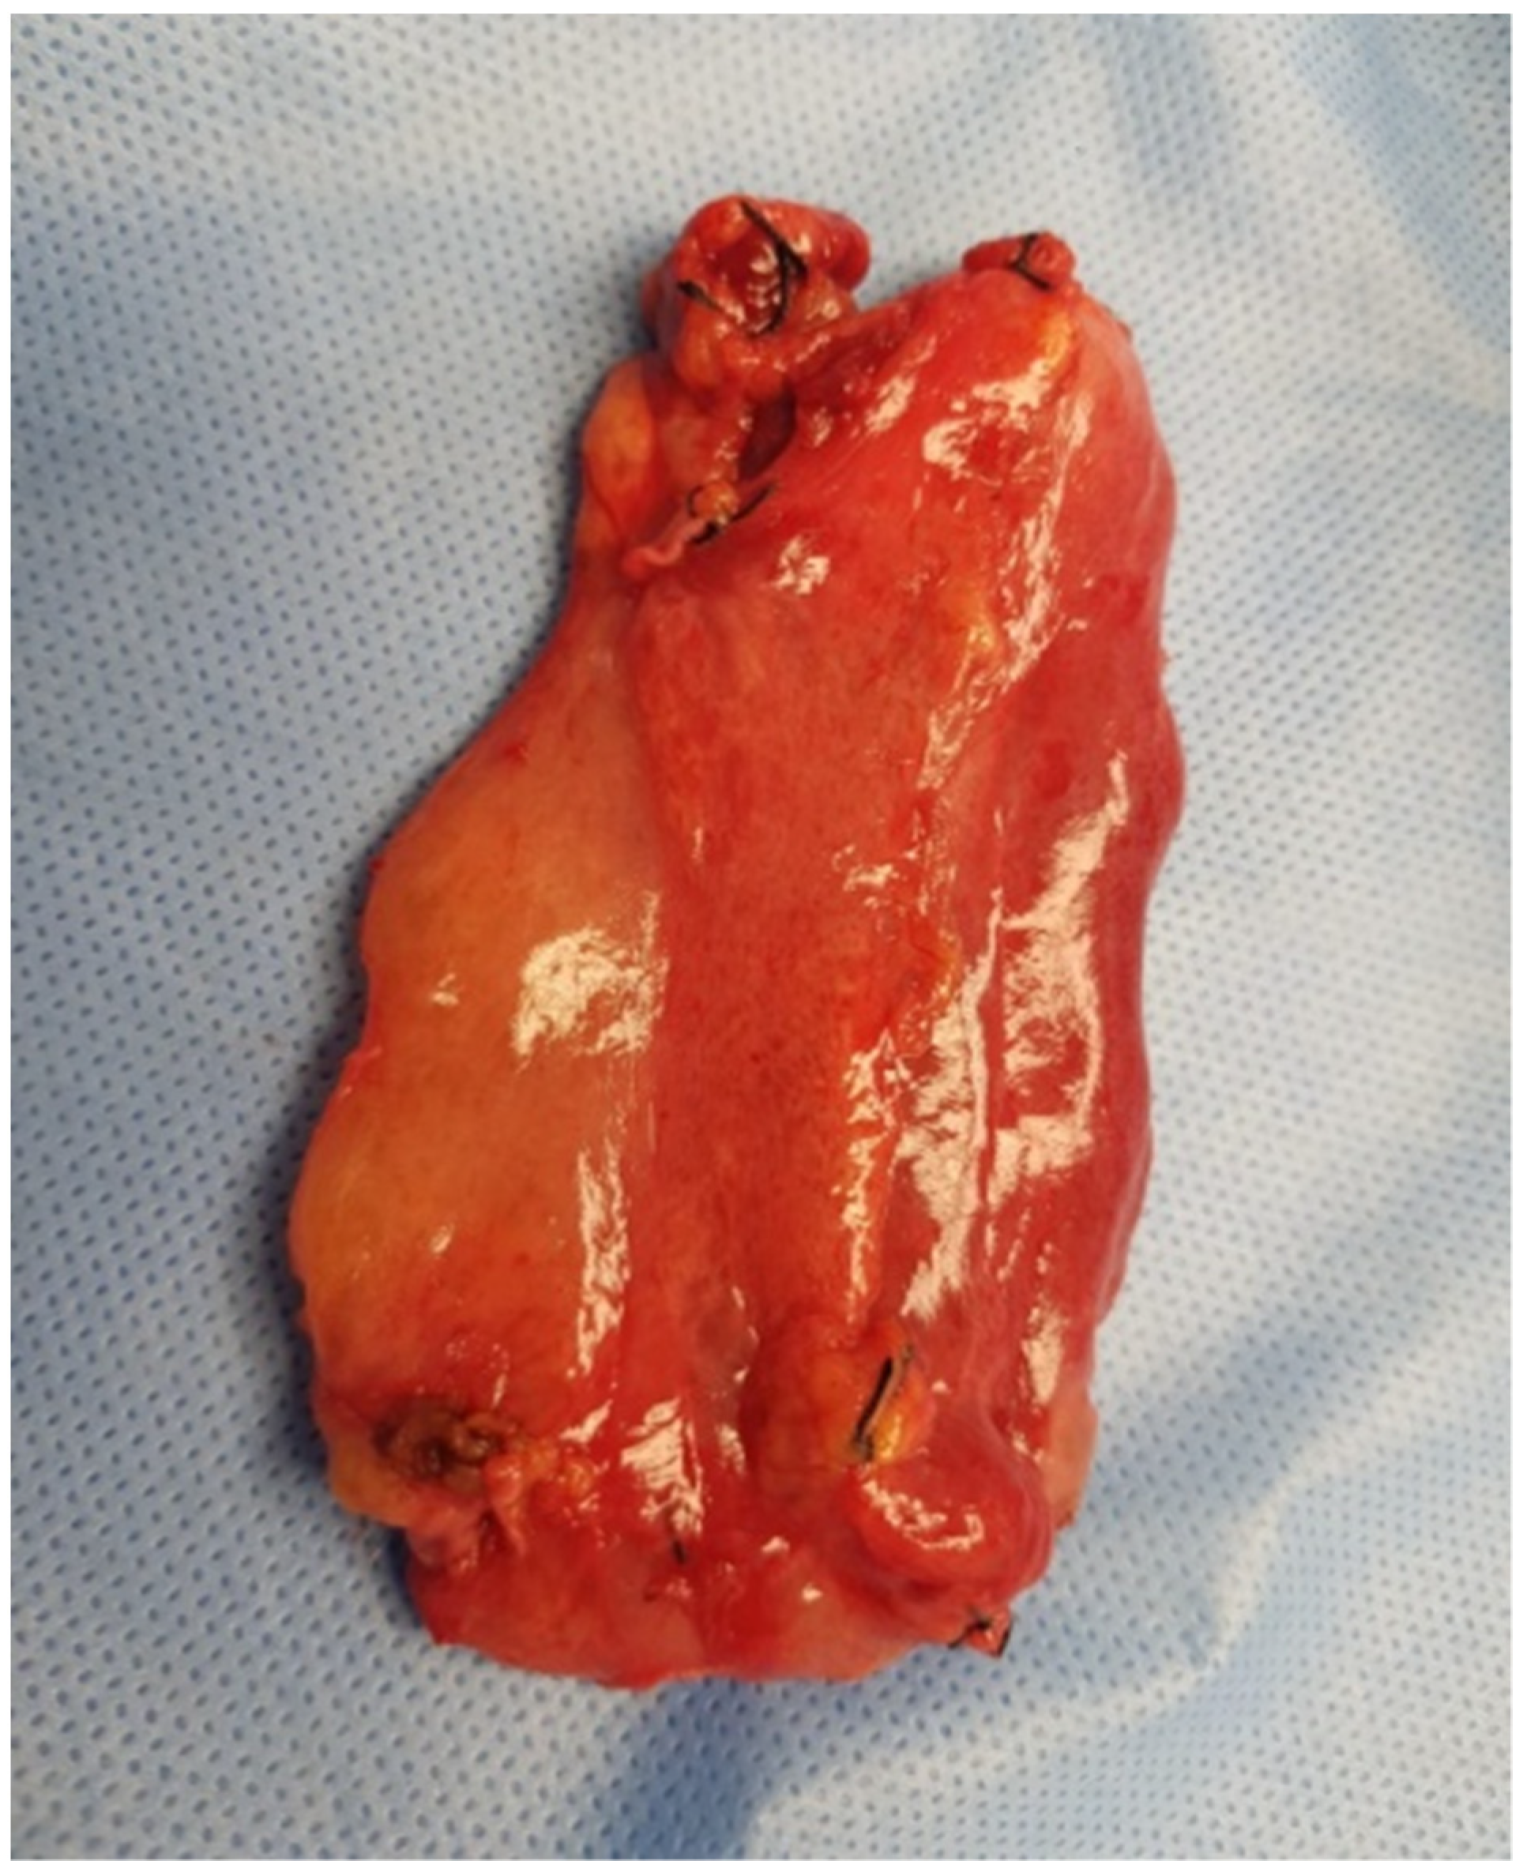

Three-phase computed tomography (CT) scan revealed an extensive mass measuring 10 × 4 cm between the left segments of the liver and the lesser curvature of the stomach. The lesion was well-defined, fluid dense, and did not contain solid elements. Within it, there were vessels with an undistorted course. The mass occupied the space in front of the body and tail of the pancreas, descending further down the back of the stomach and duodenum. (Figure 1A,B).

Figure 1. (A,B) Computed tomography (CT) image of the abdominal cavity. There is a visible mass located at the lesser curvature of the stomach (orange arrows).